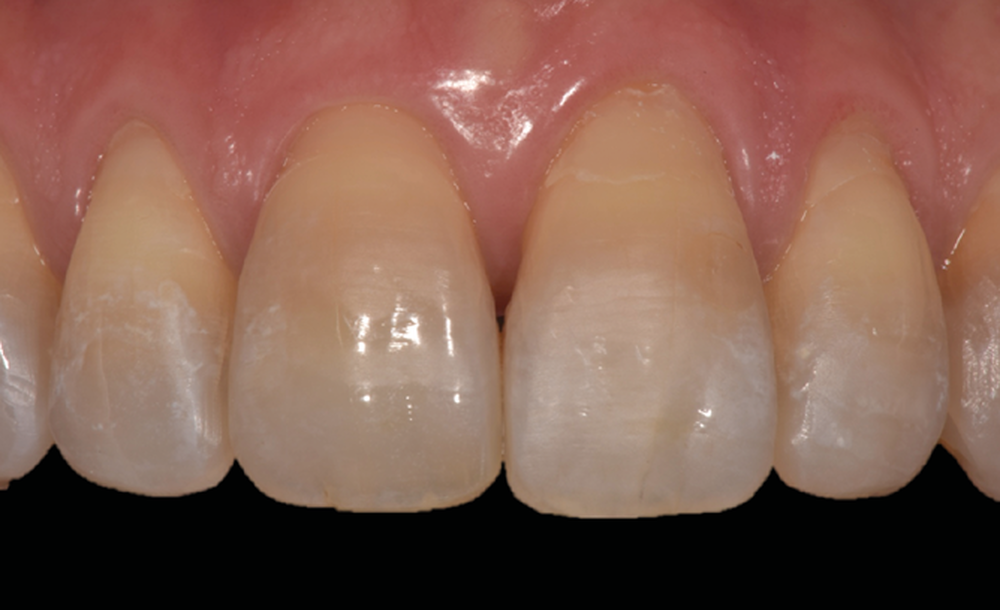

Le Pr Olivier Sorel insistera sur l’importance du respect des formes et des proportions anatomiques, pour éviter de voir apparaître, notamment chez les adultes, de très inesthétiques triangles noirs lors de la phase d’alignement (fig. 6a-b). Il présentera sa démarche diagnostique (évaluation de la forme des dents et de la dysharmonie dento-dentaire, fig. 7a-c) et l’intégration de la réduction amélaire proximale au plan de traitement, afin de s’assurer, en fin de traitement, la présence de papilles gingivales et donc d’un sourire harmonieux (fig. 8a-d).

Les Drs Marie Clément et Clara Marcoux aborderont ensuite les différents apports de la dentisterie esthétique aux traitements orthodontiques. Les problèmes de dyschromies isolées ou généralisées, congénitales ou acquises seront développés ainsi que les anomalies de proportions dentaires (dents riziformes…), le maquillage (transformation d’une canine en incisive latérale…) et le remplacement des dents antérieures. Les auteurs présenteront l’intérêt du Digital Smile Design dans le diagnostic et la communication et l’arsenal thérapeutique à notre disposition pour améliorer la satisfaction de nos patients (éclaircissement, traitement des taches de l’émail, composites stratifiés, fig. 9a-d).